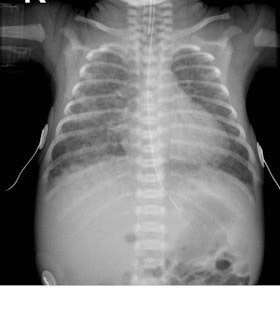

-The chest radiograph appearances of pneumonia are not specific, and frank lobar consolidation as seen in adults and older children is rare. More commonly, there is coarse opacity of one or more regions of the lung parenchyma. However, these appearances can also be seen with retained fetal lung fluid, meconium aspiration, aspiration of gastric contents, and pulmonary haemorrhage. Pleural effusions are not uncommon in infection, but again may be seen with other conditions.-Group B Streptococcus can have an appearance similar to Respiratory Distress Syndrome (Surfactant Deficiency), although the granulation is typically more coarse.